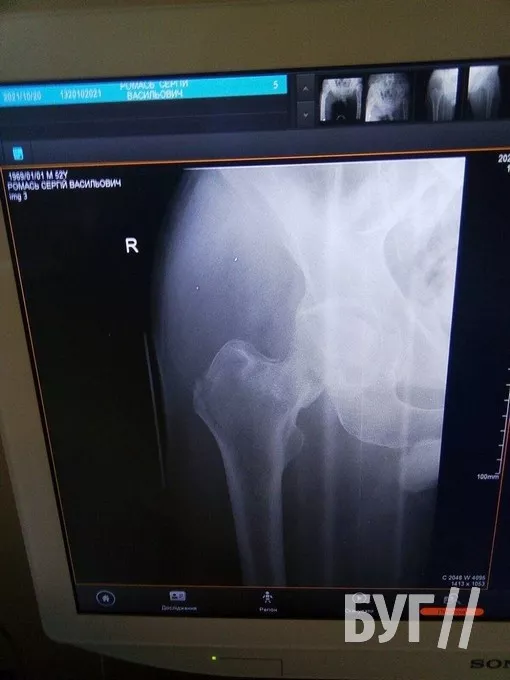

У 52-річного чоловіка, який проживає у селі Суходоли, два переломи стегнових кісток і розтрощений кульшовий суглоб.